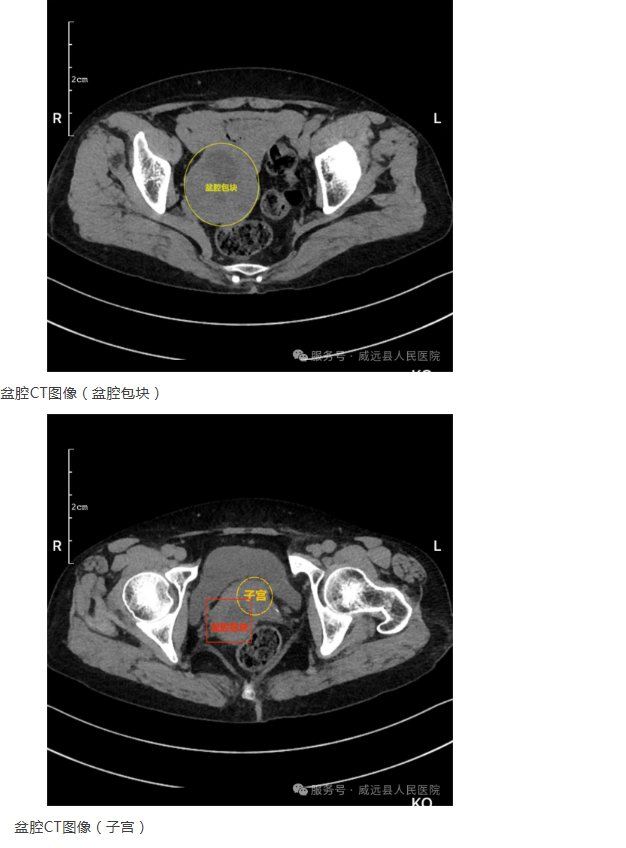

多学科协作破迷局 | 一例罕见“伪装”为附件肿瘤的小肠间质瘤成功诊治纪实